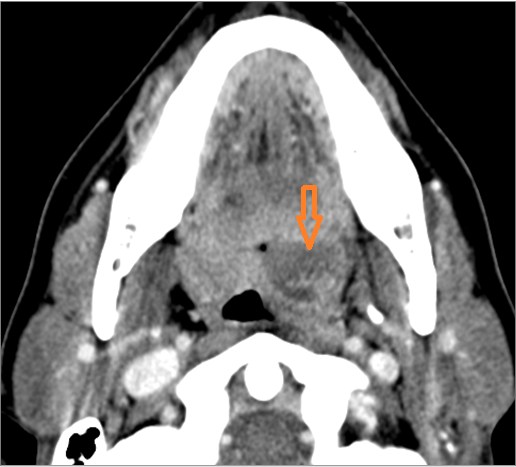

9 month old male presenting to the emergency room with poor feeding, fever, respiratory distress and possible retropharyngeal abscess or suppurative retropharyngeal adenitis.Exam

| Retropharyngeal Lymph Nodes | Correct Answer | Your Answer |

|---|---|---|

There is reactive retropharyngeal lymphadenopathy. |

Yes | NA |

There is suppurative retropharyngeal lymphadenopathy. |

If there is suppurative retropharyngeal adenopathy what is the maximum short axis dimension of the largest suppurative node. Measurement |

< 2cm | NA |

There is edema/abscess within the adjacent parapharyngeal and retropharyngeal spaces. |

There is edema/abscess within in the prevertebral or paravertebral spaces. |

Impression

Expert Answer

Pharyngitis with suppurative retropharyngeal adenitis.